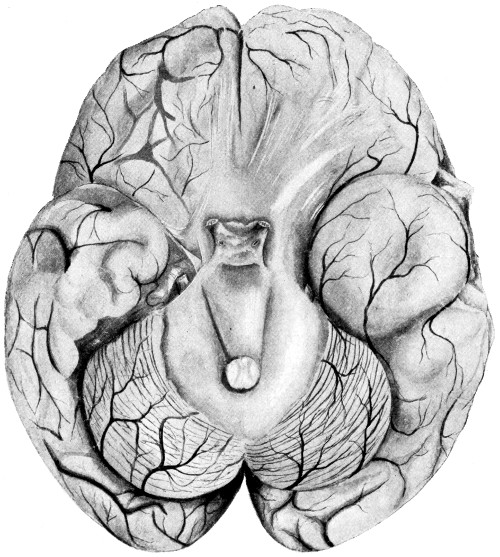

Fig. 2. Cranio-cerebral Topography. 1, 1, Reid’s base-line; 2, 2, A line parallel to the above at the level of the supra-orbital margin; 3, The middle meningeal artery; 4, The anterior branch; 5, 5, 5, The three sites for trephining; 6, The posterior branch; 7, The site for trephining; 8, The point for trephining to reach the descending horn of the lateral ventricle; 9, The lateral sinus; 10, The inion; 11, The mastoid process; 12, Macewen’s suprameatal triangle; 12a, The mastoid antrum; 12b, The facial nerve; 13, The suprameatal and supramastoid crests; 14, 14, The temporal crest; 15, The temporal fossa; 16, The external angular frontal process; 17, The tendo-oculi attachment; 18, The lachrymal groove. (Reproduced, by the permission of Mr. H. K. Lewis, from the author’s work on ‘Landmarks and Surface-markings’.)

The cerebellum lies wholly beneath the tentorium cerebelli, and it is obvious that, in operations carried out over this portion of the brain, the surgeon is limited in his field of exposure, above by the line of the lateral sinus, and on either side by the posterior border of the mastoid process. The division between the halves of the cerebellum may be represented by a line drawn vertically downwards from the external occipital protuberance to the nuchal region. This line also represents the surface-marking of the occipital sinus and falx cerebelli.

This artery is given off from the internal maxillary; after a short extra-cranial course it enters the skull through the foramen spinosum, and soon divides into two main terminal branches. The site of division corresponds to a point situated just above the centre of the zygoma.

The anterior branch passes at first in a forward and upward direction towards the anterior inferior angle of the parietal bone, and then turns upwards and backwards towards the vertex of the skull. The main ‘danger zone’ in the course of this vessel may be mapped out by taking points which lie respectively 1, 11⁄2, and 2 inches behind the external angular frontal process and an equal distance above the upper border of the zygoma. A line uniting these three points represents that part of the anterior division of the middle meningeal artery which is most liable to injury and which therefore most frequently requires exposure.

The uppermost point may, however, be regarded as the ‘site of election’ for exposure of the artery, as, in trephining over either of the two lower points, difficulty may be experienced in the removal of the disk of bone, since the posterior border of the great wing of the sphenoid tails off on to the anterior inferior angle of the parietal bone in such a manner that to effect a clean removal of the disk is often impossible. Another disadvantage to trephining low down lies in the fact that in about 30 to 40 per cent. of cases the artery occupies, in that situation, a canal in the bone.

The posterior branch passes almost horizontally backwards, parallel to the zygoma and supramastoid crest, towards the posterior inferior angle of the parietal bone. The vessel can readily be exposed[6] by trephining over the point at which a line drawn backwards from the upper border of the orbit, parallel to Reid’s base-line,[1] cuts another line directed vertically upwards from the posterior border of the mastoid process.

Both branches of the middle meningeal artery possess important relations to the cortex cerebri, the anterior branch passing upwards in relation to the precentral or motor area, traversing, from below upwards, the motor speech area (on the left side of the head), the centres for the movements of the face, upper extremity, trunk, and lower extremity. The posterior branch, on the other hand, passes backwards in relation to the temporo-sphenoidal lobe, one of the so-called ‘silent areas’ of the brain. Throughout their course the middle meningeal vessels lie between the dura mater and the bone.

The lower limit of the cerebrum can be mapped out in the following manner: From a point situated about 1⁄2 inch above the nasion a line is drawn outwards which follows the curve of the upper border of the orbit as far as the external angular frontal process, thence curving upwards and backwards to the Sylvian point (see below). The temporo-sphenoidal lobe sweeps forwards to the posterior border of the malar bone, and its lower limit lies practically flush with the upper margin of the zygoma. At and behind the ear the lower limit of the cerebrum corresponds to the suprameatal and supramastoid crests, subsequently following the curve of the lateral sinus from the mastoid process to the external occipital protuberance.

The Sylvian point represents the site of divergence of the three limbs of the Sylvian fissure. It lies 11⁄4 inches behind the malar tubercle and 11⁄2 inches above the upper border of the zygoma. The main posterior horizontal limb passes backwards and upwards to a second point situated 3⁄4 inch below the parietal prominence.

The vertical limb is directed upwards for about 1 inch, whilst the anterior horizontal limb passes forwards for about the same distance.

This, from a surgical point of view,[7] the most important fissure of the brain, is represented as follows: A point is taken in the median antero-posterior line which lies 1⁄2 inch behind the mid-point between nasion and inion, and from this point a line is drawn, for 31⁄2 to 4 inches, towards the mid-point of the zygoma. This line is inclined to the median antero-posterior line at an angle of 671⁄2° (three-quarters of a right angle).

In the representation of these two fissures, two points require to be determined—the malar tubercle and the lambda. Allusion has already been made to the former; the latter is usually readily located as the point of intersection of the sagittal and lambdoid sutures. A line uniting these two points corresponds in its middle third to the temporo-sphenoidal fissure, and in its posterior inch or so to the external parieto-occipital sulcus, a fissure separating the occipital and parietal lobes of the brain.

The researches of Sherrington and Grünbaum,[2] Campbell,[3] and others tend to show that the cortical motor areas are situated entirely anterior to the central fissure or fissure of Rolando, extending above well over on to the mesial aspect of the brain, though not so far as the calloso-marginal fissure, and in the downward direction to within a short distance of the fissure of Sylvius. In the posterior direction the motor area includes the anterior boundary and part of the bottom of the fissure of Rolando, whilst in front it spreads, by means of gyri annectantes, on to that part of the brain which lies anterior to the precentral sulcus. The anterior termination is indefinite, but the motor strip is, on an average, not more than 3⁄4 inch in breadth.

This motor strip corresponds, from above downwards, to the movements of the contralateral lower extremity (toe to hip), trunk, upper extremity (shoulder to fingers), neck and face. It is a point of some general utility to bear in mind that the temporal crest intervenes approximately between the regions responsible for the movements of the upper extremity (above the crest) and those for the movements of the head and face (below the crest).

On the left side of the head—in normal right-handed individuals—the motor speech area of Broca corresponds to the third left frontal convolution, in the angle between the anterior and posterior horizontal limbs of the Sylvian fissure.

The ‘primary registration’ of ‘common sensation’ occurs in the post-central gyrus, immediately posterior to the fissure of Rolando. This tactile area occupies a position behind the fissure of Rolando[9] similar in extent to that occupied by the motor area in front. It commences at the bottom of the fissure of Rolando and extends backwards over rather more than half the exposed area of the post-central convolution. It reaches down to near the Sylvian fissure and extends over on to the mesial aspect of the brain. Furthermore, it is probable that sensation in any given part lies on more or less the same level as the corresponding motor area.

Immediately posterior to the tactile area and occupying the posterior and upper part of the post-central convolution, the area responsible for muscle-sense is situated.

Stereognosis—memory pictures, object perception, &c.—is referred to the superior parietal lobe.

Primary visual impressions are received in the occipital lobe, more especially on the mesial aspect thereof.

Finally, the four areas concerned in speech—motor speech, writing, reading, and hearing—are anatomically separated from one another and yet closely associated, so much so that one can hardly be involved without the other. The motor speech centre of Broca has already been mentioned as occupying—in right-handed individuals—the posterior part of the third left frontal convolution. Writing lies immediately above and in front, in the posterior part of the middle frontal gyrus, auditory impressions are received in the posterior and upper part of the first temporo-sphenoidal lobe, whilst the power of reading is dependent on the integrity of the supramarginal and angular gyri (see also Fig. 57).

Smell and Taste lie in close relation to the anterior pole of the temporo-sphenoidal lobes.